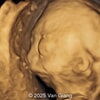

A 30-year-old G2P1, with an unremarkable history, presented to our office in the 21st week of her pregnancy for a routine second-trimester screening. Our examination revealed the following findings: